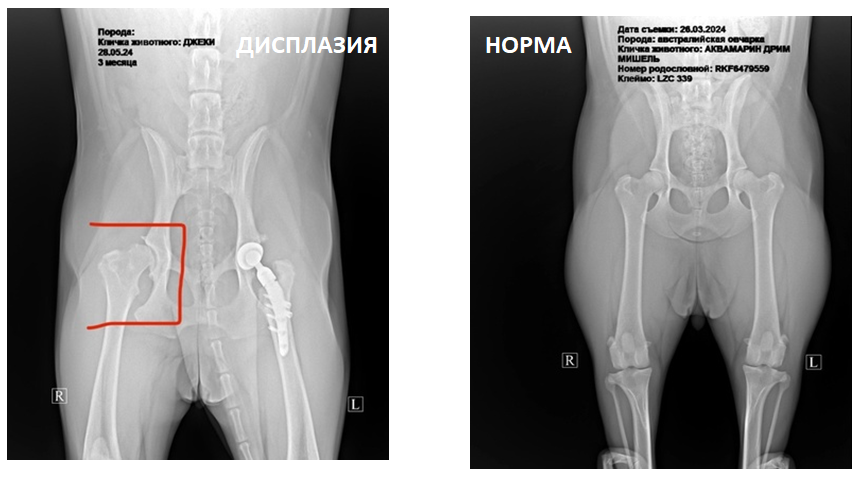

слева снимок моей Джеки, сейчас у нас с обеих сторон стоят протезы

Норма – бедренная головка и вертлужная впадина плотно прилегают к друг другу и анатомически повторяют формы друг друга, где связочный аппарат между костьми стабилизуют и плотно удерживают суставную капсулу целиком.

Дисплазия – соответственно противоположность норме, где растянута связка и нарушены формы сустава, что приводит к боли во время движения из за трения и воспаления, в усугублении добавляется подвывих это когда головка сустава выходит, но еще способна вернуться обратно, естественно это дико больно, а в тяжёлой форме происходят вывихи полноценные, и сустав окончательно разрушается.